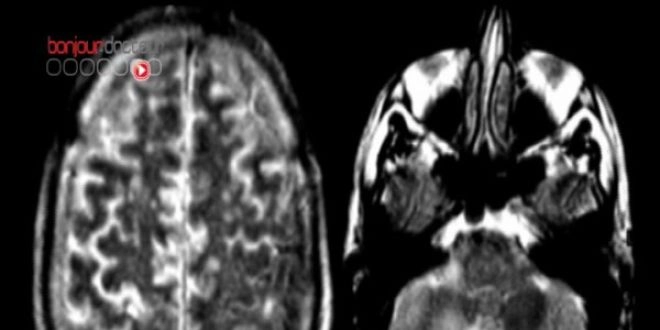

Une IRM pour comprendre l’ironie

Ce réseau de neurones, connus depuis une dizaine d’années, permet d’interpréter les intentions des individus qui nous entourent et de cette façon, il participe à la compréhension du langage. Il représente ce que les sciences cognitives appellent « la théorie de l’esprit ». Il inclut des zones très spécifiques dans le cerveau : les jonctions temporo-pariétales droite et gauche, le cortex préfrontal médian et le précunéus.

Ils ont alors réalisé une IRM fonctionnelle sur 20 personnes lors de la lecture de 18 de ces histoires choisies au hasard parmi les 20. A ce stade, les sujets ne savaient pas que le test portait sur l'ironie.

Les imageries ont alors montré qu’au moment de la lecture de la phrase déterminante, le réseau « théorie de l'esprit » s'activait plus lorsque la phrase était ironique. Les chercheurs en ont conclu que le réseau participe directement aux processus de compréhension de l'ironie, ce que l’on peut étendre à la compréhension du langage.